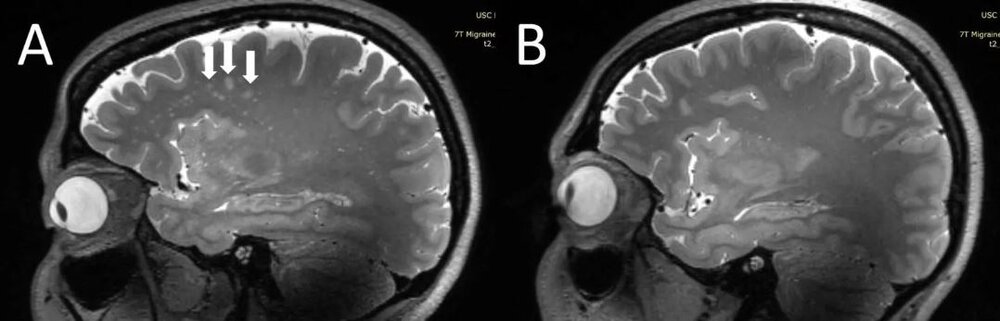

ژو و همکارانش، به دنبال آن هستند تا ارتباط میان میگرن وبزرگ شدن فضاهای اطراف عروقی را درک کند. این محققان با بهرهگیری از MRI ۷T با وضوح فوقالعاده بالا، به مقایسه ساختاری تغییرات میکروواسکولار (رگهای خونی بسیار ریز) در انواع مختلف میگرن پرداختند. ژو در این رابطه گفت:« این اولین بررسی با استفاده از MRI با وضوح فوقالعاده بالاست که در آن به بررسی تغییرات میکرو واسکولار مغز در پی بروز میگرن، بهویژه در فضاهای اطراف عروقی پرداخته میشود. از آنجا که MRI ۷T قادر است تا تصاویری با وضوح و با کیفیت به مراتب بالاتری نسبت به دیگر دستگاههای MRI از مغز ارائه دهد، میتوان از این دستگاه برای تشخیص تغییرات جزئیتر و ریزتری که بعد از بروز میگرن در بافت مغز ایجاد میشود، بهره برد.»

محققان، در جریان این بررسی فضاهای بزرگ شده اطراف عروقی را در سنتروم سِمی اوال (بخش مرکزی ماده سفید مغز) و غدههای قاعدهای را اندازهگیری کردند. افزایش و شدت ماده سفید مغز (ضایعهای که در MRI به روشنی مشخص است) با بهرهگیری از مقایس Fazekas اندازهگیری شد. خونریزیهای میکروبلید مغزی (خونریزیهای بسیار ریز در مغز) با خونریزیهای میکروبلید در آناتومی بدن با مقیاس رتبهبندی، طبقهبندی شدند. محققان در عین حال دادههای بالینی افراد از جمله دوره بیماری و شدت آن، نشانهها و علائم در هنگام انجام اسکن و وجود هاله و منطقه سردرد فرد را نیز جمعآوری کردند.

تجزیه و تحلیلهای آماری حکایت از آن داشت که تعداد فضاهای بزرگ شده اطراف عروقی در مرکز سِمی اوال مغز افراد، در بیمارانی که میگرن داشتند، به مراتب بیشتر از افراد سالم بود. به علاوه کمیت فضاهای بزرگ شده اطراف عروقی در مرکز سِمی اوال با عمق ماده سفید، از نظر شدت جدی بودن در بیماران میگرنی در ارتباط است.

ژو ادامه داد:« ما در تحقیقات درباره میگرن مزمن و میگرن اپیزودیک بدون هاله به این نتیجه رسیدیم که در هر دو دسته افراد مبتلا به این نوع میگرنها، فضاهای اطراف عروقی در مرکز سِمی اوال بزرگتر بودند. اگرچه ما هیچ تغییر قابل توجهی در شدت ضایعات بخش سفید مغز در افراد مبتلا به میگرن و افراد بدون میگرن پیدا نکردیم، ولی این ضایعات بخش سفید مغز به طور قابل توجهی با وجود فضاهای بزرگ شده اطراف عروقی مرتبط بودند. این بدان معناست که تغییرات در فضای اطراف عروقی، ممکن است منجر به افزایش ضایعات بیشتری در بخش سفید مغز شوند.»